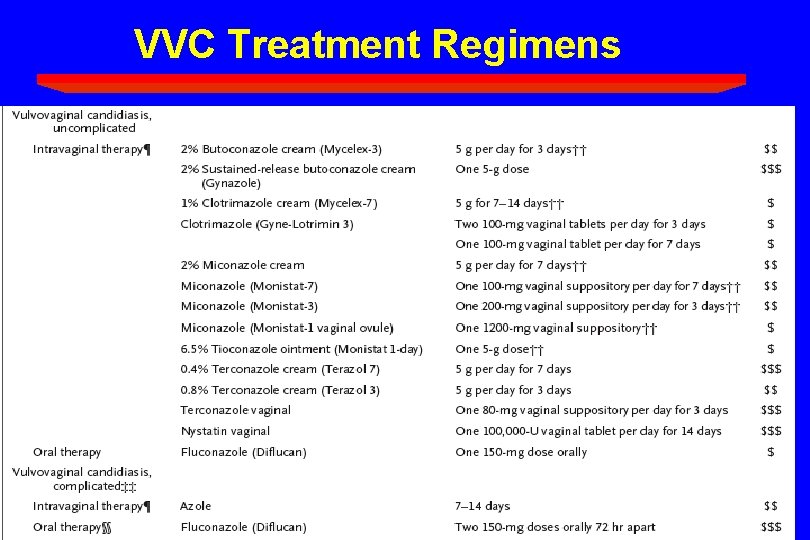

VVC Treatment Regimens